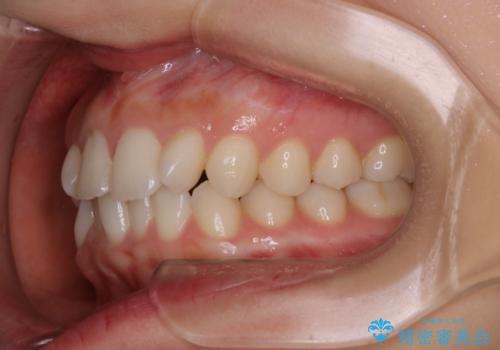

- 前から2番目の歯が捻じれていることが気になるとご相談にいらした方です。

インビザラインFULLで治療を行いました。

上の前から2番目の歯は、一般的に周囲の歯と比べて小さく、動きづらい歯であると言われています。前歯にゴムかけを行うことで理想的な位置まで歯を動かしてくることが出来ました。